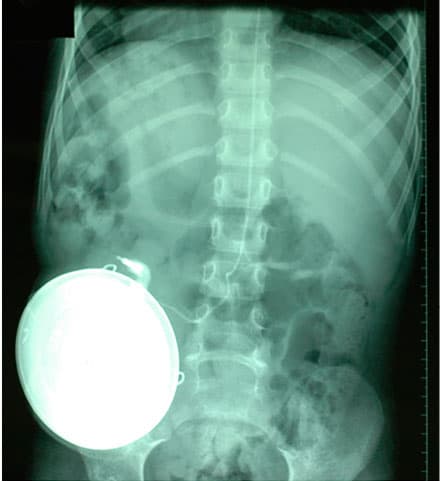

X-ray of a child with a baclofen pump and connecting intrathecal catheter.

If the test was considered positive, then the MAS score was reduced by at least one point, the child could have a pump implanted and was referred for operation following parental consent. Each operation was performed in general anaesthesia, and antibiotics were administered preoperatively. First, by way of a dural puncture at level L2-4, the catheter was inserted intrathecally. The catheter was then cannulated subcutaneously to one side of the abdomen and connected to the pump, then placed in a subcutaneous pocket. Two different pump types were used; either a pressure-driven pump (volume 20 or 35 ml) or an electric pump (volume 20 or 40 ml). In August 2009, electric pumps were introduced. All patients who had a pump implanted after that year received an electric pump.